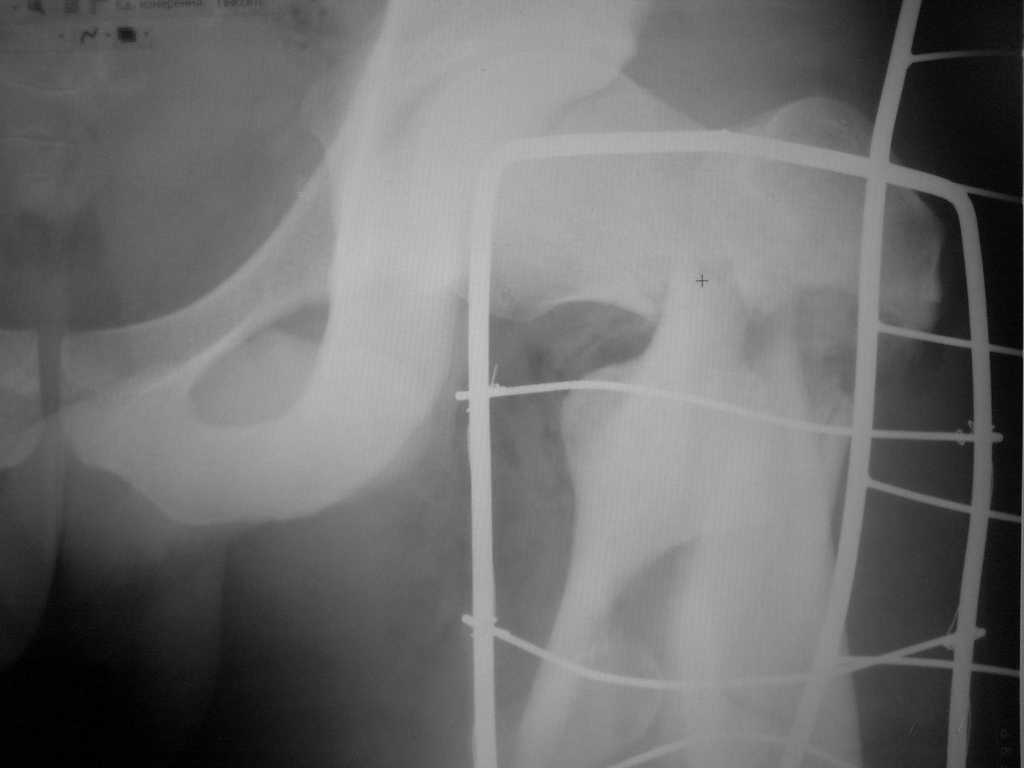

Здесь пара похожих случаев.

Увожаемый коллега,мое мнение:фиксация и\медул.блок. стержнем Gamma-long "STRYKER". Вероятно, закрыто сделать полностью может не получится. Откроетесь на 6-8 см. для репозиции промежуточного фрагмента, но только после установки стержня. Удачи!!!